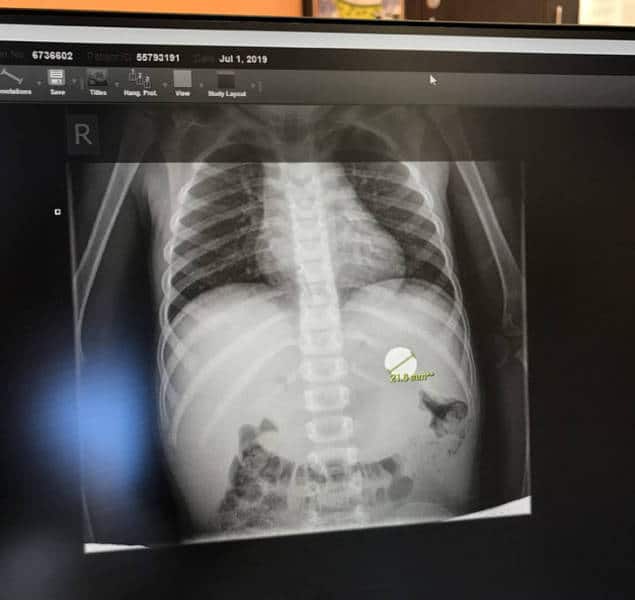

« Mon neveu qui a décidé d’avaler une grosse pièce. »

enfants parent 16